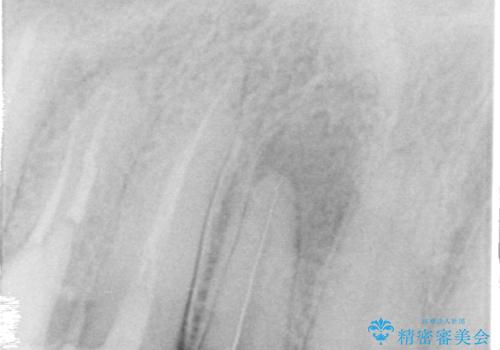

また、右上側切歯は根管治療が必要な状態でした。

右上側切歯に対して根管治療を行い、その後右上側切歯から左上犬歯まで計5本をオールセラミッククラウンで補綴する治療計画をご提案しました。